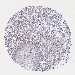

CANCER BREAST CANCER Show tissue menu

BRCA TCGA BRCA VALIDATION PROTEIN EXPRESSION

ANTIBODIES

AND

VALIDATION